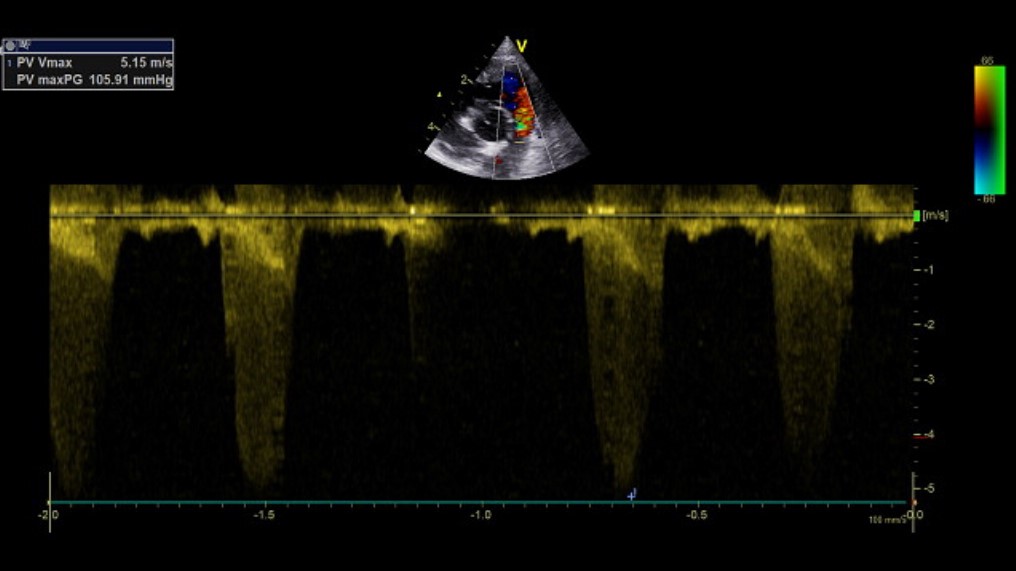

Forsnævring af lungepulsåren

Ved auskultation cranialt og højt dorsalt i hjertefeltet høres en crescendo-decrescendo mislyd – en stenosemislyd. Det er en hyppig misdannelse hos både store racer (golden retriever, boxer og så videre) og små racer (bulldogs, WHW og så videre).

Pulsåreforsnævringen gør, at højre hjerteside skal yde et langt større udpumpningstryk end normalt. Derfor udvikles en excentrisk hypertrofi af højre hjerteside med fortykkelse af muskulaturen og dilatation og trykstigning i højre ventrikel.

Der ses en voldsom turbulens i aortas udløb. Udløbshastigheden, og dermed graden af stenose, måles bedst subcostalt, hvorved proben står vinkelret på aorta. Diagnosen baseres på udløbsflowet sammen med LVOT (aortas diameter ved aortas klaptilhæftninger).